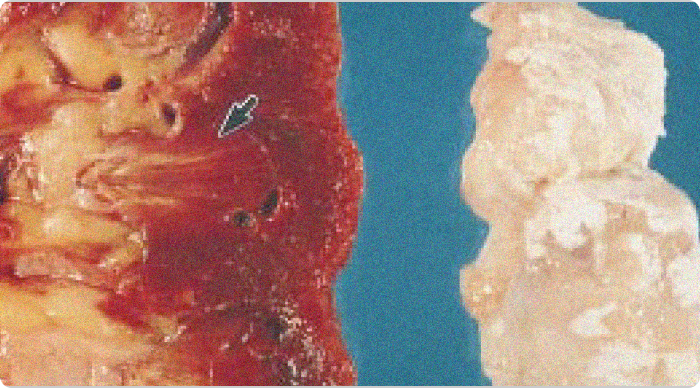

Images of gouty tophi in joint and kidney

Gouty tophi in joint and kidney. Chalky white urate deposits are visible in the articular cartilage (right). The corresponding kidney (left) shows yellowish areas in the pyramids (arrow) representing fibrosis and urate deposits.1

Adapted from Nickeleit V, et al. Nephrol Dial Transplant. 1997;12:1832-1838.

KRYSTEXXA has not been studied to reverse damage to the kidneys or any of the body's organs.

Photo of tophi from gout in spine

(A) Intraoperative photograph of the chalky white material at the right L2-L3, L4-L5 facet joints (white arrows).

(B) Histological examination (H&E, 100x) shows amorphous tophaceous deposit with a multinucleated giant cell reaction.2

Adapted from Lu H, et al. Medicine (Baltimore). 2017;96:e7670.

KRYSTEXXA has not been studied to reverse damage to the spine or any of the body's organ.